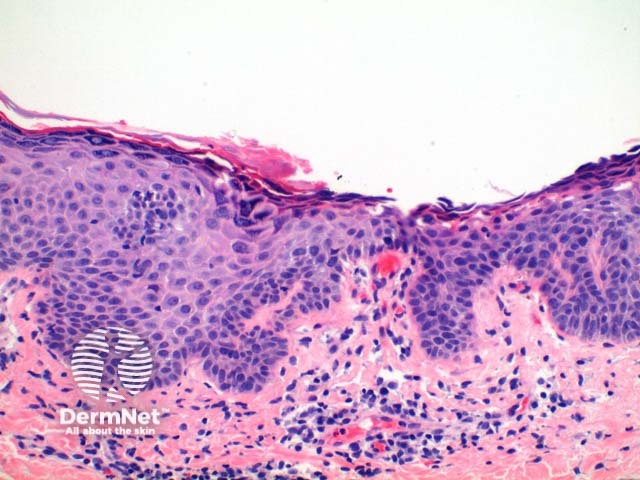

The low power view of the histology of pemphigus foliaceus is of a superficial epidermal blistering process. The low power clues include loss of the stratum corneum, increased prominence of the granular layer, or visible superficial epidermal separation with blister formation (Figure 1). At higher magnification subtle acanthloysis and spongiosis can be seen within the stratum granulosum, extending into the stratum corneum (Figures 2 and 3). This can form separation within the superficial epidermis, or as mentioned above, lead to complete loss of the stratum corneum. The prominent granular layer is seen as hyperchromasia of the nuclei within dyskeratotic cells in this layer, similar to the grains seen in Dariers disease (Figures 4 and 5).

Figure 2